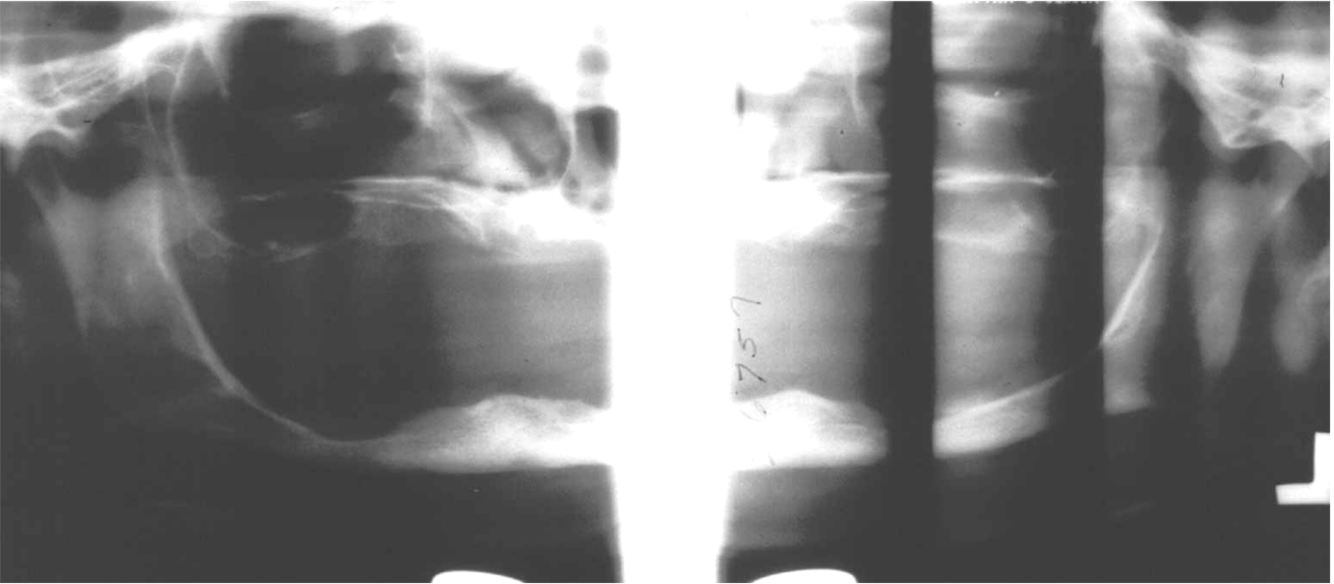

What is this positioning error?

Teeth behind focal trough

- When teeth are behind focal trough they look more enlarged – magnified horizontally

- Cant see the spine at all because its out of the focal trough